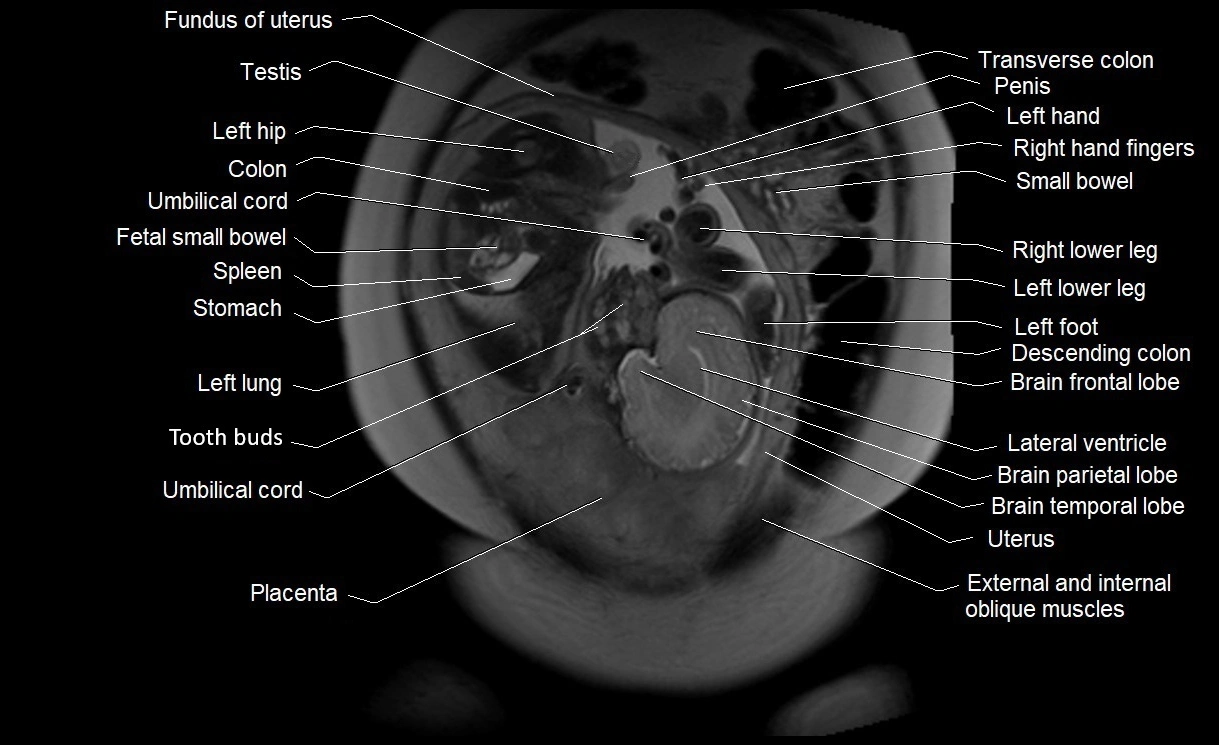

MRI Appearance

T2 HASTE (T2 GRE):

• Amniotic fluid shows very bright hyperintense signal

• Provides natural contrast against fetus and placenta

• Small particles (vernix) may appear as scattered hypointense foci within bright fluid